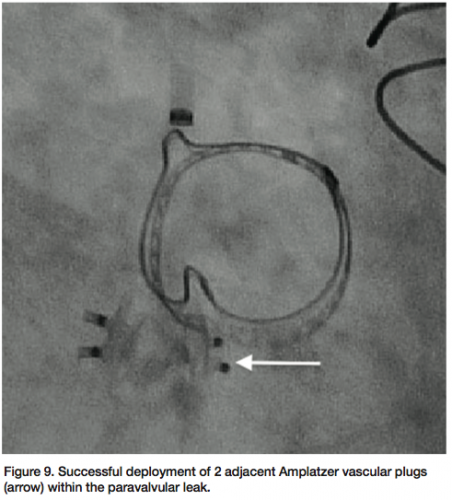

The patient underwent general anesthesia and endotracheal intubation for TEE evaluation in the cardiac catheterization laboratory. The paravalvular leak was crossed using a 6 French multipurpose diagnostic catheter and angled Glidewire, followed by a 6 French shuttle sheath (Cook Medical) over an Amplatz stiff wire (Figure 7). Using TEE and fluoroscopy, an 8 mm Amplatzer vascular plug II (AGA Medical) was deployed successfully, with persistent moderate regurgitation from the anteromedial region of the paravalvular aortic leak (Figure 8). The defect was

recrossed with a 5 French EBU guide catheter (Medtronic), followed by placement of a second 8 mm Amplatzer vascular plug (Figure 9). Final angiography (Figure 10) and TEE (Figure 11) of the paravalvular leak after two adjacent vascular plugs demonstrated no significant residual paravalvular leak. All catheters and sheaths were removed, with hemostasis achieved using a vascular closure device. The patient was discharged home without complications the following day.